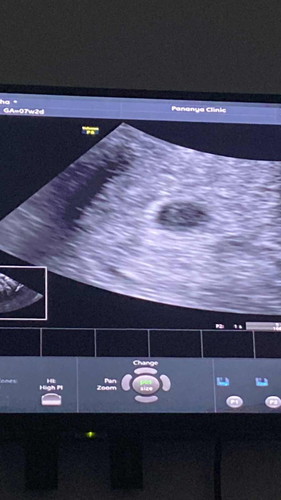

หมอบอกน้อง 4สัปดาห์ มีแต่ไข่แดง แต่ฝั่งในมดลูกแล้ว ตอนนี้เห็นในตต.ท้องลมเยอะมาก เครียดเลยคะ🥲#ท้อง4สัปดาห์ #ท้องสอง